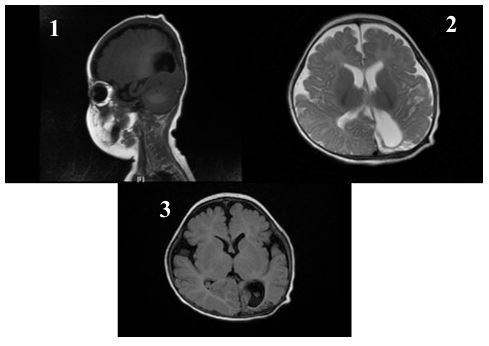

After 11 days of treatment, physical examination revealed mild swelling and redness in the posterior fontanelle area at the midline and slightly to the left of the occipitoparietal region, ap proximately 3 cm in diameter, soft in texture with slight fluctua t ion. The brain enhanced MRI showed abnormal enhancement signals in the right parietal lobe and the left parieto-occipital area, suggesting an infectious lesion. Brain tissue was under compression and midline shift were observed (Figure 1). After the child was diagnosed with brain abscess, he was transferred to the neurosurgery department for further treatment. The sur gery of brain abscess drainage and external subdural effusion drainage was performed under general anesthesia with tracheal intubation. During the operation, a cyst infection was observed, and it eroded the underlying dura mater, with tight adhesion between the cyst wall, brain tissue, and dura mater surrounding the dura mater, thickening of the dura mater, and necrosis of the surrounding brain tissue. The infected cyst wall was separated from the surrounding dura mater, carefully dissected from the lateral to the midline to the brain tissue interface, with protec t ion of the sagittal sinus at the midline, and deep erosion of the falx cerebri. The infected cyst had broken through to the oppo site side. The right dura mater was incised, and the infected cyst and necrotic brain tissue were thoroughly removed, connecting both sides. The defected skull was about 1x3 cm in size (Figure 2). Infected DSTs and ruptured DCs with parieto-occipital brain abscess were resected (Figure 3). Postoperative pathological examination showed that purulent inflammation with abscess formation was formed. After surgery, the child was treated with meropenem (0.2 g Q8H 21d) and linezolid (0.05 g Q8H 21d) to resist infection. The child recovered smoothly after surgery, and follow-up showed good growth, with no recurrence or neuro logical sequelae (Figures 4 & 5).

Figure 1: Preoperative imaging examination for brain abscess. (A) Preoperative cranial CT showing parietal bone defect. (B) Preoperative enhanced MRI: T1-weighted image showing extracranial soft tissue mass, adjacent intracranial cystic lesion (thin arrow), rim enhancement, inferior parietal bone destruction (thick arrow), brain abscess and subdural effusion (asterisk). (C) DWI of cranial MRI at 1 month after birth showing high signal in the left parietal intracranial region. (D) Preoperative DWI showing abscess formation.

Figure 4: One-month postoperative follow-up examination. (1) Abnormal signals in the right parietal and left parieto-occipital lobes decreased in size, with partial softening and gliosis. (2) Bilateral parietal short T1 signals slightly decreased. (3) Minor left frontotemporal subdural effusion decreased from previous; bilateral frontotemporal epidural space slightly widened.

The diagnosis of brain abscess can be made through cranial CT or MRI. CT scans are more effective for older children because the high-water content in the brains of newborns reduces the contrast between normal and affected tissues [10]. Enhanced MRI is the best method to prove the specific and non-specific expressions of intracerebral infectious inflammatory reactions, as it can more accurately determine the extended range of sinus tract extension and its relationship with abscesses, cysts, and venous structures. This imaging assessment is vital for early diagnosis and timely intervention. MRI typically shows ring-enhancing lesions on T1 scans after injecting contrast agents, and the DWI is shown on central high signal, with corresponding low ADC values. Dermoid cysts present as high signal on T1WI, and their signals on T22WI are variable, also showing high signal on DWI. Reviewing this patient’s cranial MRI at one month of age and comparing the same DWI plane at two months, the high signal observed at one month was likely a dermoid cyst that could be easily overlooked clinically. Therefore, we believe that for lesions especially near the midline, further neuroradiological examination is necessary to exclude potential DSTs and DCs.